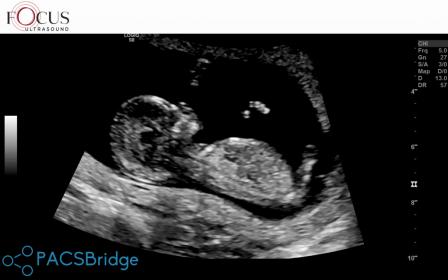

5th baby nub opinions please! 13th week

I swayed pink for a sister for my dd so I'll be honest I'm looking for hope this is a girl. So far only had boy comments elsewhere although some of the mods are 'maybe' boy, not 99%.

Atomic you've seen one of my pics in my swaying thread already but these are some more I've got from pausing the video (every micro second!). Baby was not in perfect sagittal position. I did during the scan see flashes of a long white, flat nub but she didn't capture it. She was trying to image the legs for nicer pics!

The skull/face reminds me of DDs scans but I've dreamt this bub is a boy which also happened just before I found out DS3 was a boy.

Gestation is 12+6 by OPKs & BBT, 13+5 by CRL.Attachment 43684Attachment 43685Attachment 43686Attachment 43687Attachment 43688